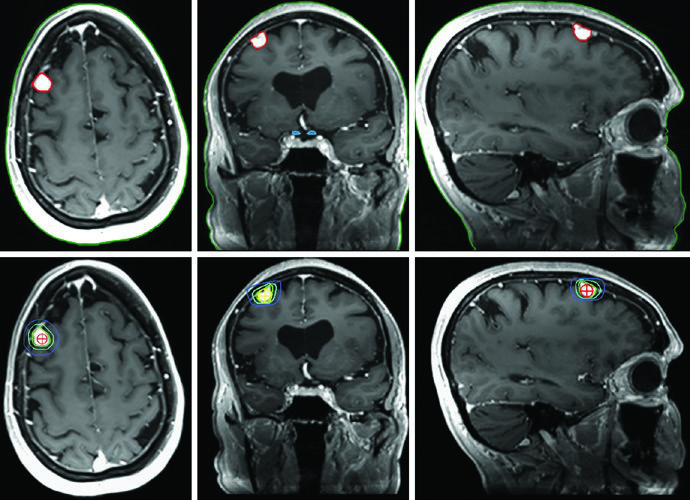

O adenoma secretor de GH da Figura 29.11 demonstra tratamento com SRS a 24 Gy. O tumor toca a margem medial da carótida cavernosa e se estende lateralmente entre as alças da carótida, com envolvimento do seio cavernoso. A dose ao quiasma, nervos ópticos e tronco encefálico permaneceu abaixo de 8 Gy. Na Figura 29.12, o adenoma não secretor mostra invasão do seio cavernoso direito e extensão suprasselar — após ressecção, o tumor residual na sela e no seio cavernoso persistiu.

A Figura 29.13 mostra o planejamento fracionado do mesmo paciente: GTV em coral, CTV com margem de 0,5 cm anatomicamente restrita em teal, PTV com expansão adicional de 0,3 cm. Tronco encefálico, quiasma e nervos ópticos aparecem como OARs delineados. Para macroadenomas, quando a invasão do seio cavernoso é difícil de visualizar, a recomendação é incluir o seio cavernoso inteiro no GTV. Conhecer o tipo de material implantado na sela (músculo, gordura ou retalho de septo nasal) ajuda a diferenciá-lo de tumor residual.